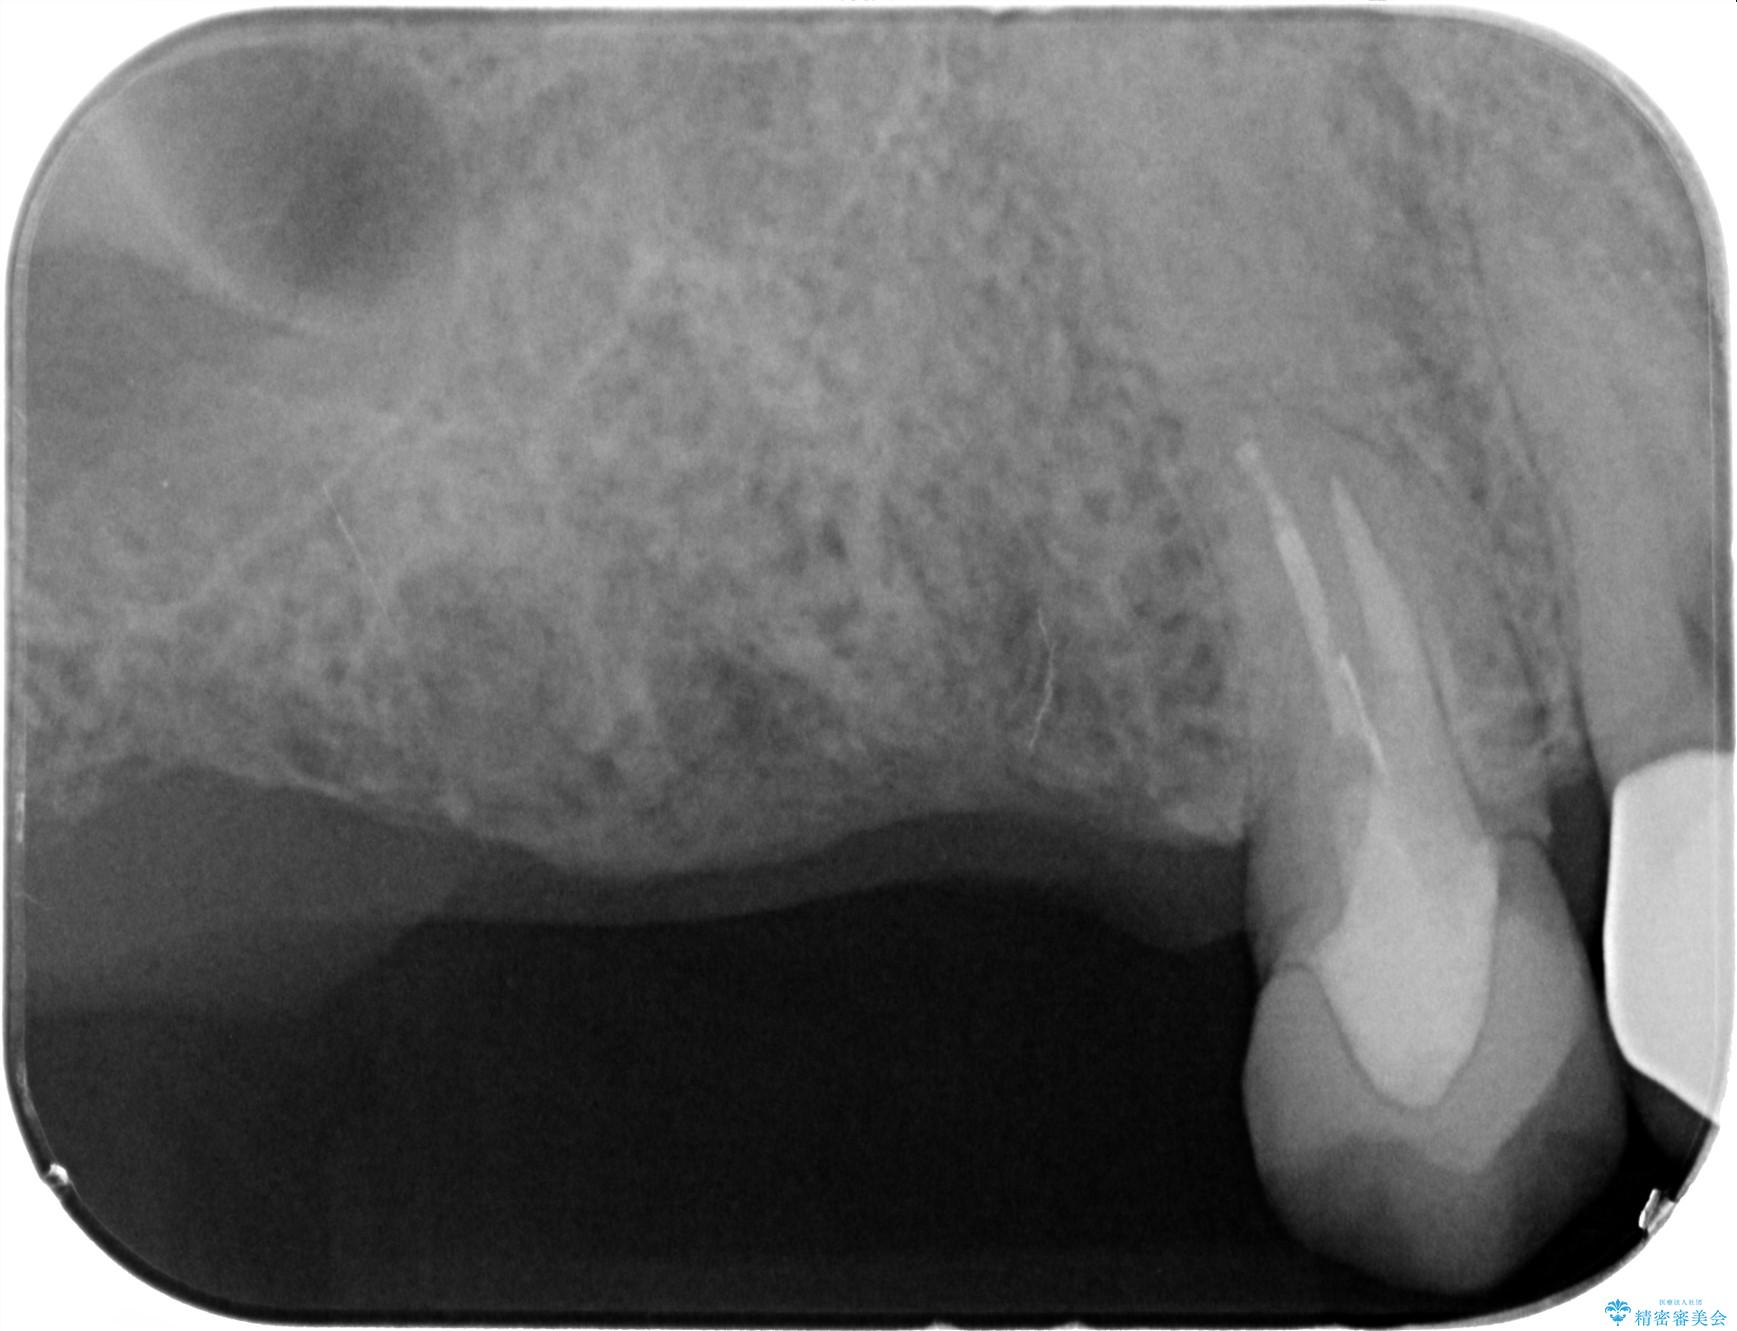

- 歯を抜いたまま放置してしまい、「やはりしっかりと噛めるような状態にしてほしい」とインプラント治療を希望され来院されました。

人工歯根であるインプラントを埋入することで奥歯でまたしっかりと噛める咬合機能を回復します。